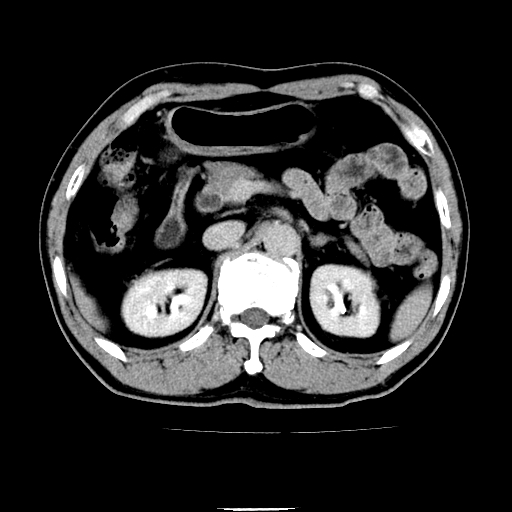

以下是引用chenqiong在2010-3-25 20:56:00的发言:[br]1、胆囊炎,胆囊息肉[br]2、肝内胆管及胆总管扩张,胆总管下端结石[br]3、十二指肠乳头旁憩室

以下是引用zxl51642在2010-3-26 10:47:00的发言:[br]胆囊炎,胆囊息肉,胆总管扩张,但未看到明显肿块,肝内胆管扩张不像恶性,炎性狭窄或阴性结石可能吧,建议mrcp,右肾小囊肿